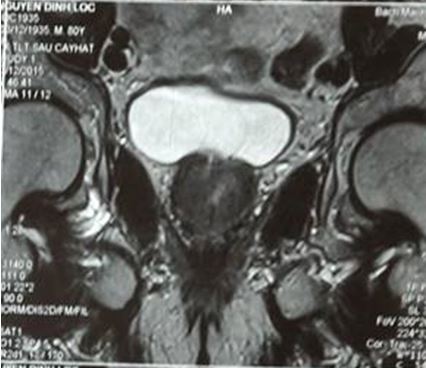

Hình ảnh MRI: khối u tuyến tiền liệt ranh giới không rõ, ngấm thuốc sau tiêm, kích thước 12 x 15 mm, chưa xâm lấn vỏ bao và túi tinh

• Chụp MRI: Không thấy khối bất thường trên hình ảnh MRI tiểu khung

Trước điều trị: tiểu són, tiểu nhiều lần; trên cộng hưởng từ khối u kích thước 12 x 15 mm, ranh giới không rõ, chưa xâm lấn vỏ bao và túi tinh; PSA = 2,4 ng/ml

Sau điều trị 7 tháng: thể trạng tốt, đi tiểu bình thường; trên hình ảnh cộng hưởng từ không có khối bất thường; PSA giảm xuống còn 0,26 ng/ml